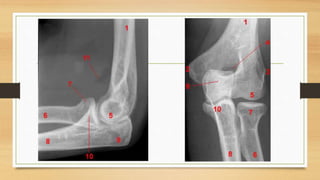

ANATOMIA

QUIRURGICA

• CAMBIO DE FORMA EN EL

HUMERO A MEDIDA QUE SE

HACE MAS DISTAL